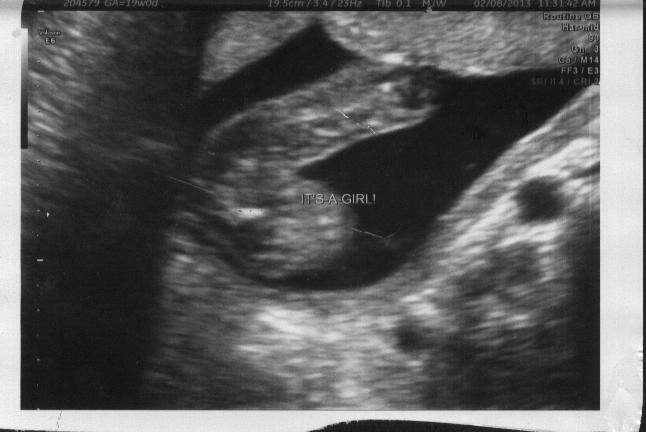

UPDATE: It's a GIRL! We are SO excited. Here's our photo from today's 19wk u/s (measuring 18+3). Feel free to confirm away that she's a little girl...I can hardly believe it. :happy:

Attachment 8778